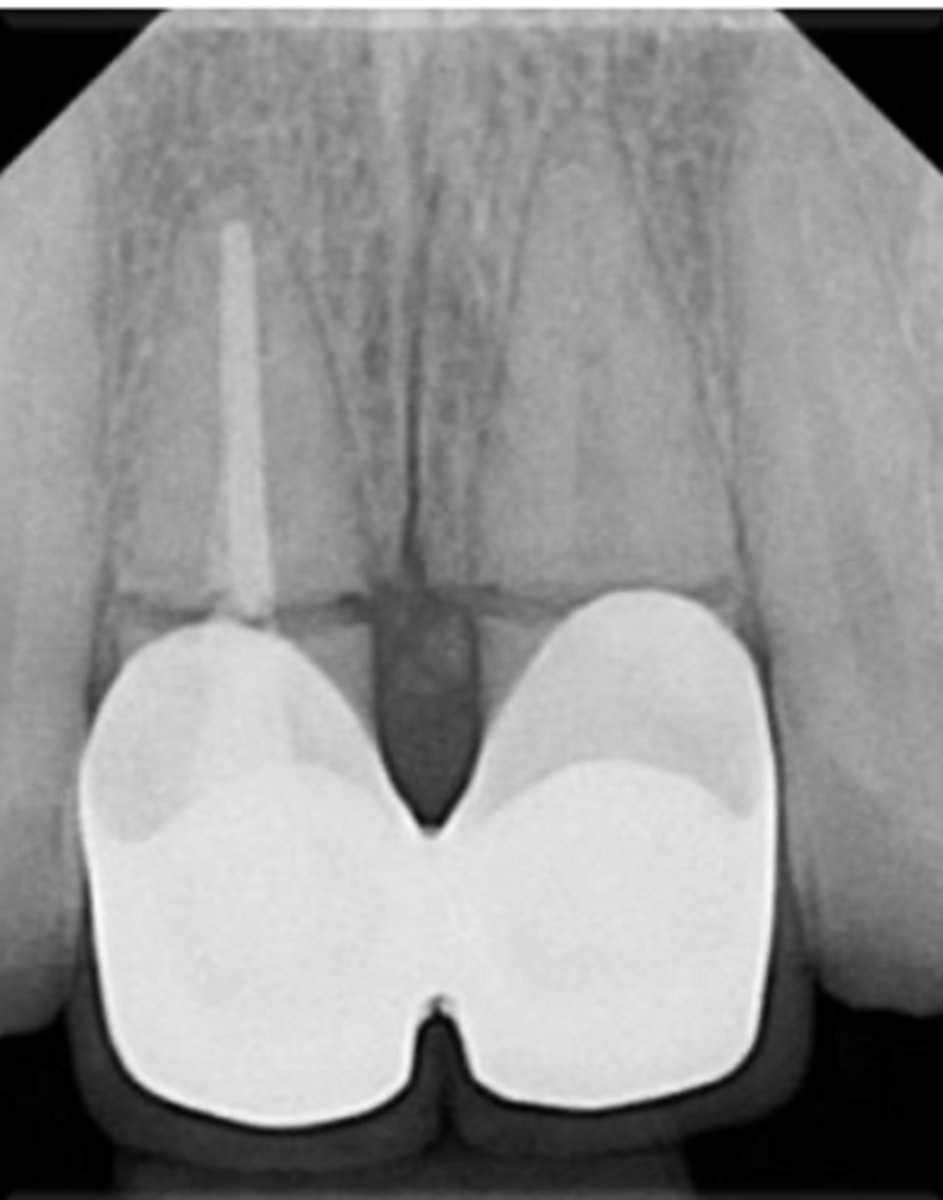

What are the radiographic findings on #13?

- Crown

- Post

ID the problem:

- Ballooning out of root canal

internal resorption

How can you confirm if a root has internal resorption?

Take a few different angles